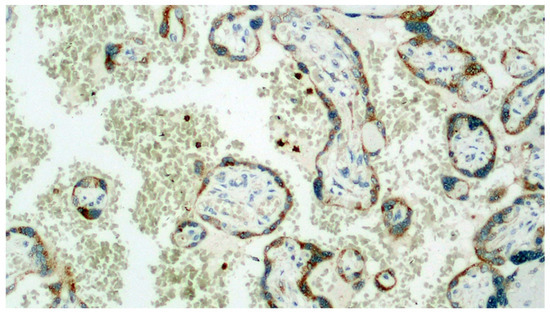

Figure 6.

Section set up for immunohistochemistry investigation using the Sars-CoV-2 anti-spikes glycoprotein antibody. Note the widespread involvement of brown-colored syncytiotrophoblast (Immunohistochemistry, IHC, 100×).

Figure 7.

Detail of the previous image. In addition to the positivity expressed by the trophoblast, a very intense positivity is observed in the leukocytes of the maternal blood (IHC, 400×).